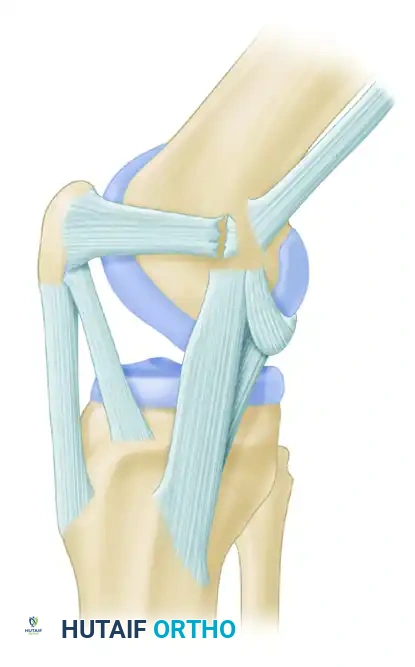

Patellofemoral instability is a complex, multifactorial pathology that demands a nuanced understanding of knee biomechanics, soft tissue restraints, and underlying bony morphology. The medial patellofemoral ligament (MPFL) is the primary passive restraint to lateral patellar translation, contributing 50% to 60% of the restraining force from 0 to 30 degrees of knee flexion. In cases of acute or recurrent lateral patellar dislocation, the MPFL is universally torn or attenuated.

Figure 47-14A: Medial patellofemoral ligament detached from the medial femoral epicondyle following an acute patellar dislocation.